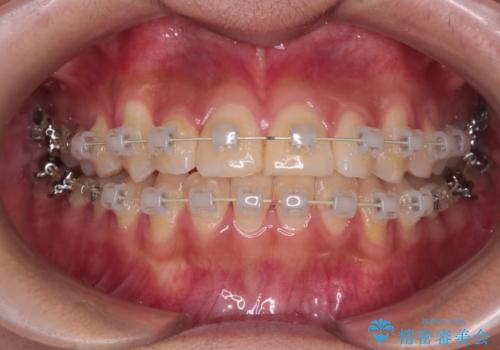

- 矯正装置

- 審美装置

- 治療期間

- 1年6ヶ月

- 治療回数

- 10-30回